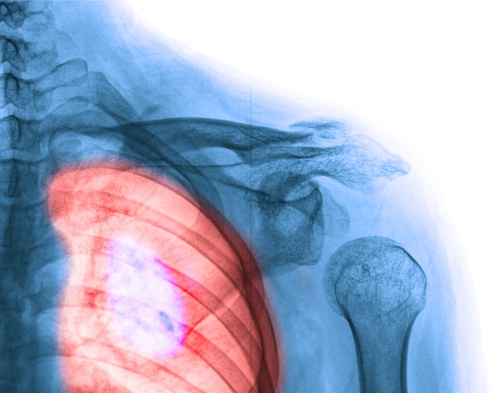

4. Cancro ai polmoni

Negli ultimi anni l’incidenza di questo cancro sta diventando molto preoccupante tra i tumori più diffusi tra le donne. Inoltre rappresenta una delle maggiori cause di mortalità sia tra gli uomini sia tra le donne. Bisogna tenerlo in considerazione.

L’80% dei casi ha origine dal tabacco. Fumare o essere esposti a situazioni in cui si inala il fumo presenta gravi conseguenza per la nostra salute. Si tratta di abitudini che possiamo evitare, che bisogna abbandonare perché, a lungo termine, possono causare numerose malattie.

Al giorno d’oggi il numero di donne fumatrici è aumentato moltissimo. Sembra che qualcosa non funzioni nelle campagne pubblicitarie e che il messaggio non arrivi come dovrebbe. Evitate di fumare per la vostra salute e per la tranquillità dei vostri cari.

A seguire alcuni sintomi di questo cancro:

- Una tosse persistente

- Dolore al petto quando si tossisce

- Fischi al petto quando si respira

- Stanchezza

- Perdita di peso

- Presenza di sangue quando si tossisce

- Sensazione di mancanza d’aria

- Russare molto forte durante la notte